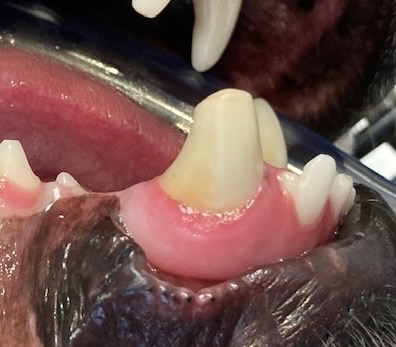

There are many indications for root canal therapy. These include (but are not limited to): fractured teeth, discolored teeth, non-vital (dead) teeth, and infected teeth. In some situations, extraction is the best choice for the patient or owner, but in many cases, treatments can be done to save the teeth.

In simplified terms, root canal therapy is removal of the pulp (blood and nerve supply inside the tooth) within the root canal and pulp chamber of a tooth. The canals are then sterilized, filled, and sealed to prevent bacteria from creating infection. The main advantage of root canal therapy is maintenance of the tooth’s form and function. Also, it is usually less invasive than extraction. After treatment the tooth is no longer alive, but all of the structures supporting the tooth are still alive. In some cases, placement of a metal crown is advised to protect the tooth from further injury.